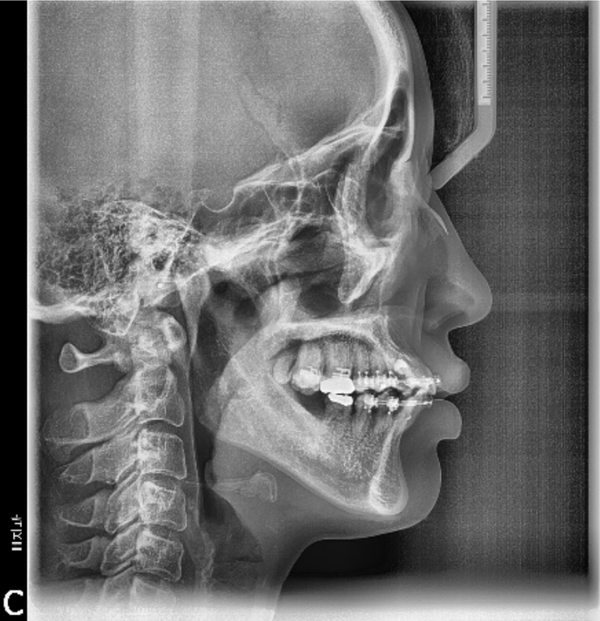

상악에서 miniscrew를 이용한 2mm 정도의 total arch distalization을 계획하였으므로 상응하는 최종교합형성을 고려하여 하악 대구치부에 임플란트식립을 진행하였고 구치부 support의 조기확립을 위해 temporary crown을 이용한 임플란트 상부보철 진행후 하악치열의 후방이동을 진행하기로 하였습니다.

하악임플란트상부보철물에 tube를 부착하되 tube slot에 각형호선이 가급적 passive 하게 들어가도록 보철물의 모양과 tube 부착위치를 조절하였습니다. 계획된 후방이동량만큼 임플란트 보철물과 전방 자연치간의 space를 형성하여 전방치열을 후방견인하였습니다.

마무리된 교합은 초진시에 동일하게 양측 Class 1 교합으로 마무리하였으며 측모두 부방사선 사진에서 보듯 교정중 발생했던 전치의 flare가 개선되었습니다.